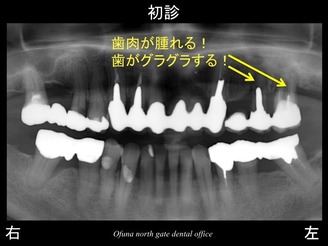

以下のレントゲンは初診時です。

上顎左側の奥歯に問題がありました。

歯肉が腫れ、グラグラとしてきたため、当医院を受診されました。

結論として、上顎左側の奥の2歯は、抜歯と診断しました。